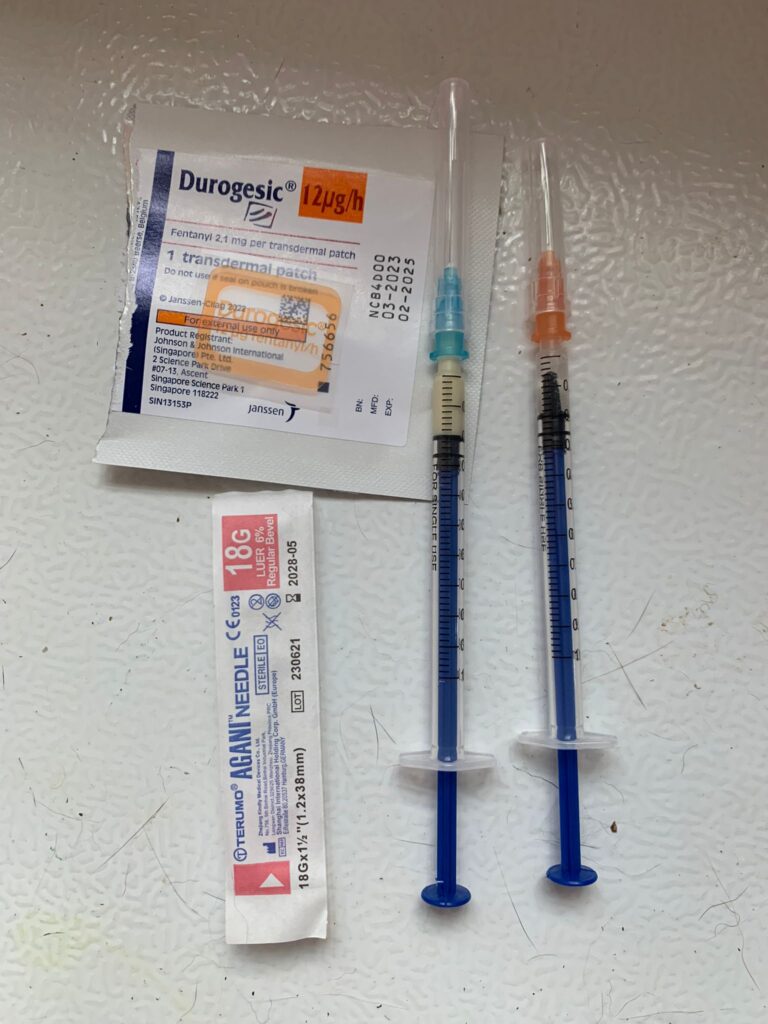

Night; did looks more in pain. Bupre in the day not enough. Have to put f patch

Morning: looks in pain. Give Subcut and bupre. I don’t have f patch in 5G. scanned on 19.4.24 no m/c.

Morning: got helper in to cut nails, steam bath and clean ears. She can handle him alone. Given Subcut bupre n put on f patch for him.

Morning: got 2 helpers in to clean up and for him: cut nails, clean ears and steam brush fur. His f patch if off, given Subcut and bupre jab

Morning; both eyes discharge look bad, clean up and put banocin on his ear. Will Subcut him and give Clav jab and bupre n put on new f patch for him

Morning: Subcut n on regular med and place new f patch n still given bupre

10am+: b4 I Subcut n give painkiller still eating ok. Subcut and given b12 b com bupre and put on a f patch (end 1.3.24)

11Am+: given bupre jab and place a f patch on his left ear.

Morning: didi constipated, saw him in 2 bins, trying to squeeze out something n can’t n he try to rub on floor – aren’t that pushing that piece in? I help him push out the 2cm piece 5/10, and he go to bin 03 and poo out another 12cm. So is that piece stuck n he is so uncomfortable. Subcut him w bupre also. His f patch still on. Can tear off soon. Need to buy more

Just status update: Today Subcut n given b12 b com also. Given bupre and fercosang also. eye more discharge. Pain. Shave his ear and place a f patch also.

Night; mmm”Don’t look good.”- pic is in pain. Tmr got to try a f patch on him again

1+pm back to 猫房 w f patch. Clean his ears and only manage to cut off some of his ears fur w scissor. I don’t have shaver for 5G have to go buy. Sigh. Put a patch on his right ear. Still v responsive to me sayang and head butt

I need to measure his weight and change to higher dose for him. I think I need to put a f patch for him